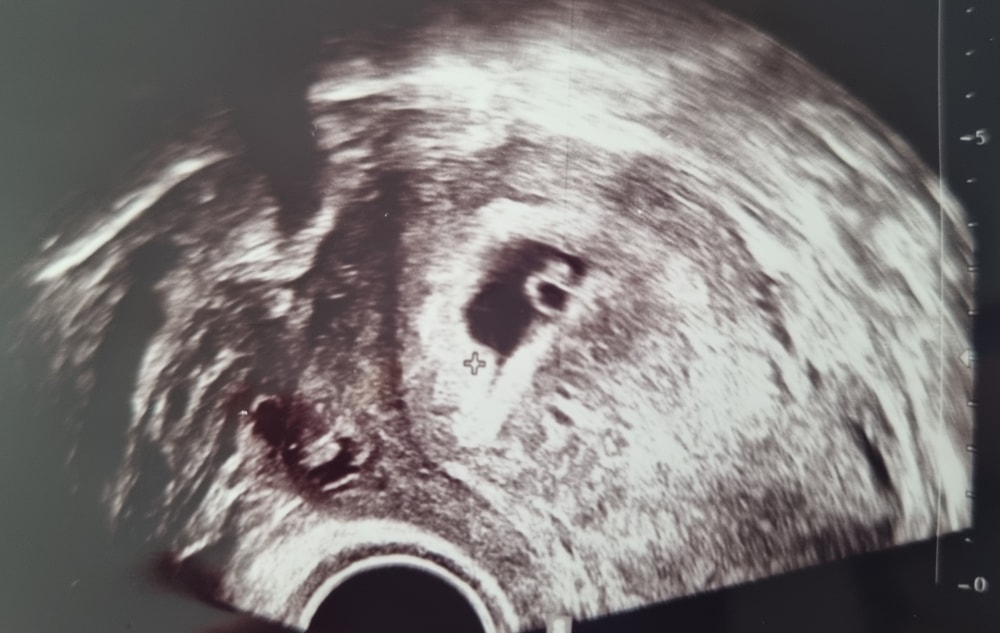

23.04 было первое узи 🥰 видно колечко красивое 😍 малююююсенькое

Было сначало страшно... Потому что делая узи, я вижу пустоту, смотрю на ре, а она серого цвета стан